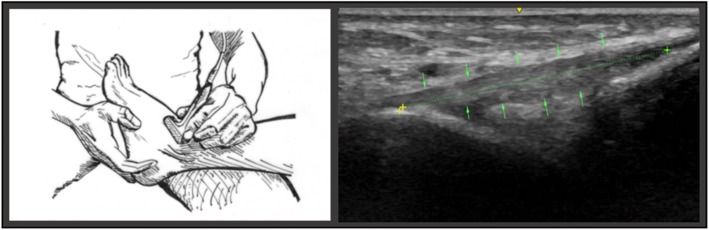

Fig. 4.

The illustration on the left portrays the examiner placing the transducer on the lateral ankle in maximal passive plantar flexion. The image on eh right depicts the measuring points of the ATFL in position C

To assume position B, the subject’s ankle was passively rotated medially by the investigator. The subject was seated on the examination table, with the calf of the designated lower extremity resting across the examiners knee and the ankle suspended. The measurement of the ATFL was conducted at maximal internal rotation stress of the talocrural joint (Fig.3) (Cho et al., 2016).

With the subject’s calf remaining on the examiners knee, position C was assumed through maximal plantarflexion of the ankle by the examiner (Fig. 4).